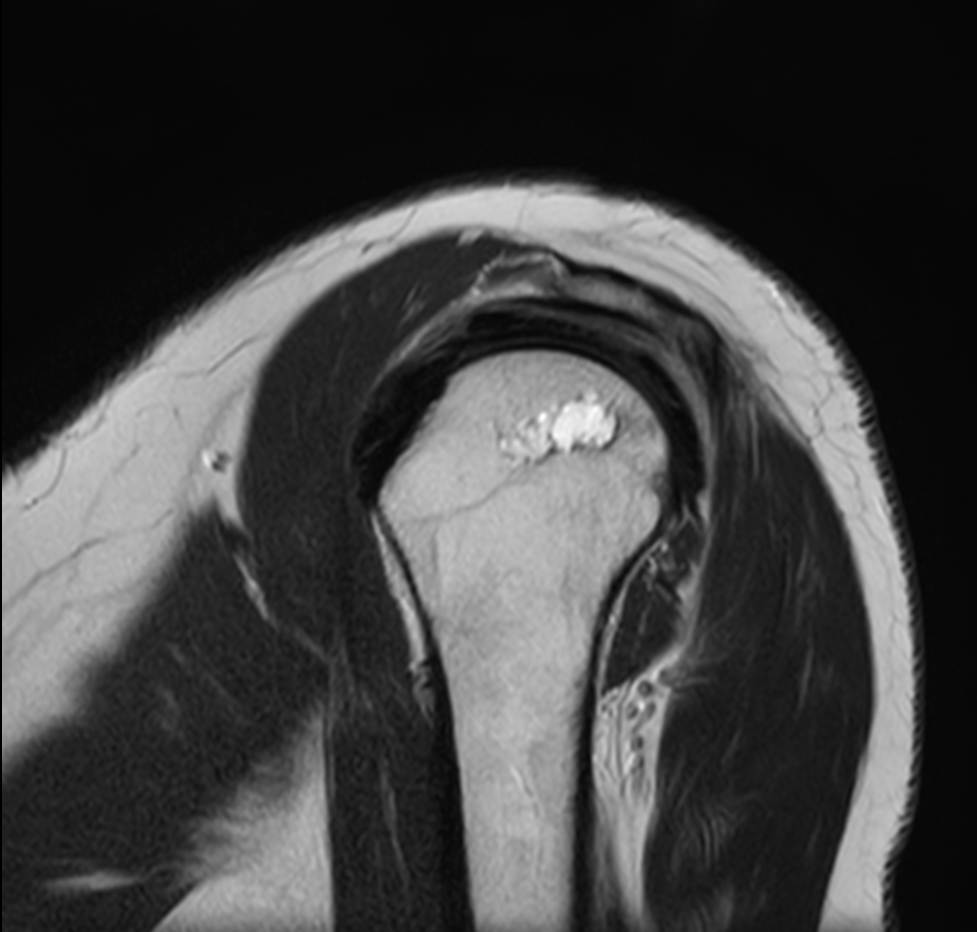

Coronal PDw TSE

Coronal T1w TSE